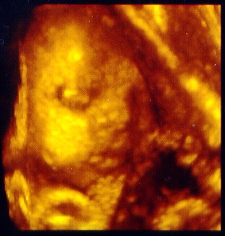

This is me at 30 weeks. Having the 3D sonogram done was Dad's idea. Both my grandmas as well as mom (of course!) and dad were there. I was approximately 3 1/2 lbs.